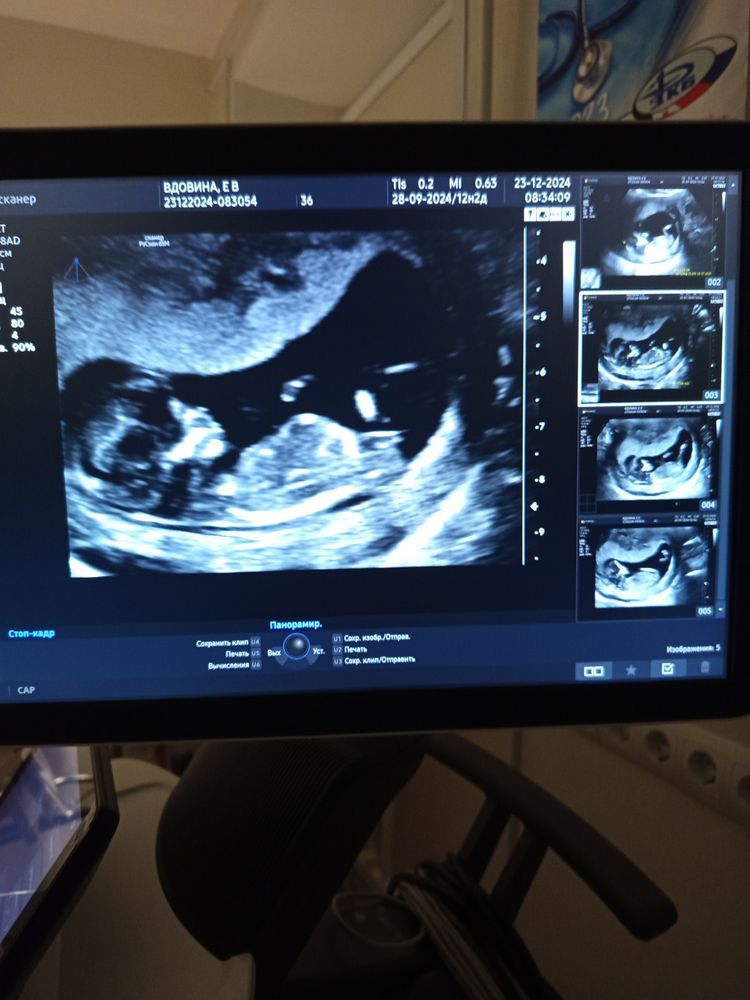

А вот в 12 + недель на скрининге уже заполнил все место. Изображение

Сходила на УЗИ Беременность 35 недель 5 дней. Хорошее ли ктг?